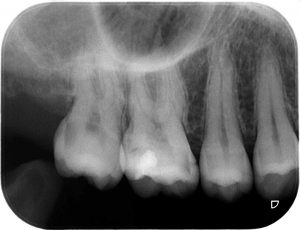

昨日、夕食のとき、「やたら右上に食べ物が挟まるな」と思っていたのですが、銀歯が外れて無くなっていました。

実は、2週間くらい前に、フロスを通していたときに外れ、セメントも使わずそのまま戻していました。

一昨日の就寝中に飲み込んだ疑い。

やはり虫歯になっています。

早く歯医者に行かなければ、、、

銀歯飲み込んだかもしれないので、お腹が痛くなれば、お医者に行かなければ、、、

私が言うのもなんですが、皆さんも歯に異常があれば、早く歯医者にかかることをお勧めします。